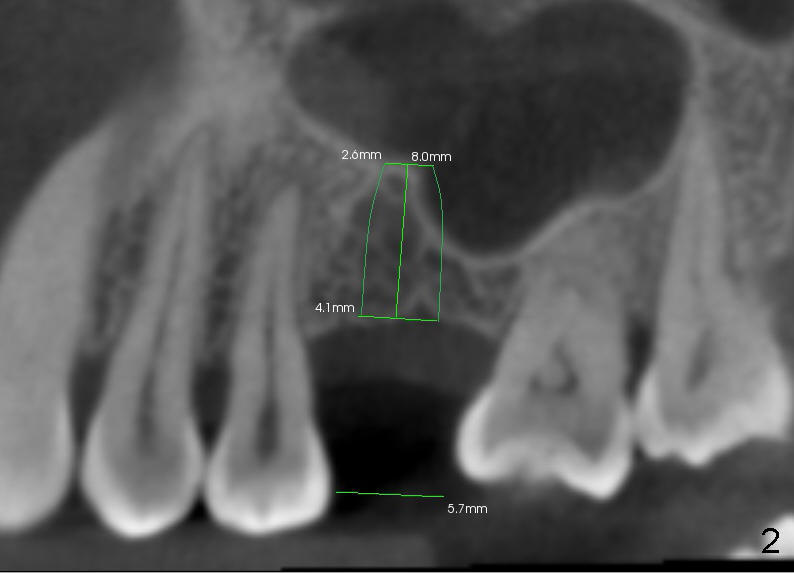

A 44-year-old lady has lost two of the 1st molars (upper left (Fig.1-3) and lower right (Fig.4-6)) for several years. Fig.1,4 are preop PAs, Fig.2,5 CT sagittal sections, and Fig.3,6 CT coronal sections. The adjacent teeth shift and tilt into the edentulous space.